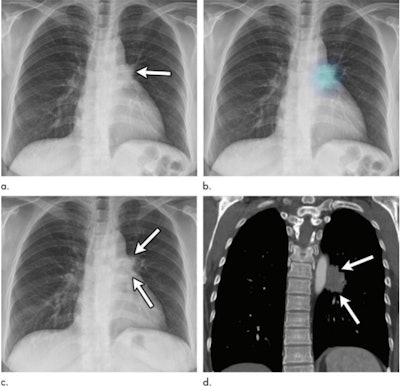

Images in a 52-year-old woman with a 10 pack-year history of smoking. (a) Initial chest radiograph shows a 2.4-cm nodule (arrow) overlapped by left hilar shadow. This lesion was undetected on the original report. (b) The deep learning-based automatic detection algorithm (DLAD) correctly detected this lesion with a probability value of 35%. Without DLAD, only two observers correctly detected the lesion; however, with DLAD, all nine observers detected the lesion and recommended chest CT for further evaluation. (c) Follow-up chest radiograph at time of diagnosis shows interval increase in lesion (arrows). (d) Follow-up chest CT image at time of diagnosis shows enhancing mass in left lower lobe (arrows). Patient was diagnosed with stage IV lung adenocarcinoma as bone metastasis was observed. The time between the initially overlooked chest radiograph and pathologic diagnosis was 447 days. Images and caption courtesy of the RSNA.

Images in a 52-year-old woman with a 10 pack-year history of smoking. (a) Initial chest radiograph shows a 2.4-cm nodule (arrow) overlapped by left hilar shadow. This lesion was undetected on the original report. (b) The deep learning-based automatic detection algorithm (DLAD) correctly detected this lesion with a probability value of 35%. Without DLAD, only two observers correctly detected the lesion; however, with DLAD, all nine observers detected the lesion and recommended chest CT for further evaluation. (c) Follow-up chest radiograph at time of diagnosis shows interval increase in lesion (arrows). (d) Follow-up chest CT image at time of diagnosis shows enhancing mass in left lower lobe (arrows). Patient was diagnosed with stage IV lung adenocarcinoma as bone metastasis was observed. The time between the initially overlooked chest radiograph and pathologic diagnosis was 447 days. Images and caption courtesy of the RSNA.Using AI with chest radiography could go a long way to improve patient care, the team concluded.